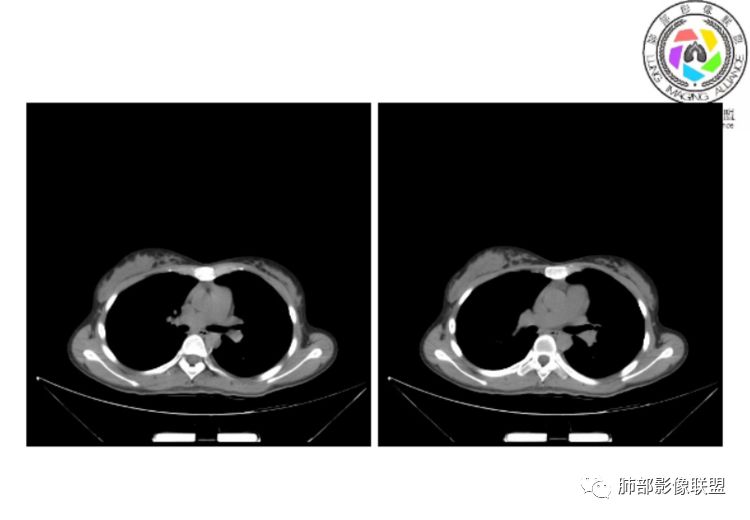

小微:右肺下叶斑片状密度增高影,抗炎治疗6天后复查,双肺下叶出现斑片状密度增高影,排除炎性病变,D2聚体特别高,考虑肺栓塞,肺梗死,建议增强扫描。王开金江津中心医院呼吸科:@岳微-辽宁PLA234医院放射科?支持,患者年轻女性,胸痛主诉,使用雌激素,高危人群,心率快,d二聚体升高,右下叶斑片加肺动脉明显增宽,抗感染无效,要考虑PTE,建议肺动脉ctpa。傅昌瑜:19岁,女性,右侧胸痛2天,发热以中度热为主,D—二聚体升高,肺动脉主干增宽,病灶位于胸膜下,抗感染后增多,近来有服用炔雌醇环丙孕酮片2周期史,诊断:肺栓塞,下一步完善肺CTPA检查。阿仙奴:青年女性,急性起病,胸痛入院,月经不调史,目前服用孕酮片。流感抗体阳性,d二聚体升高,无低氧血症。右肺下叶基底段胸膜下磨玻璃样改变,肺动脉增宽,治疗过程出现发热,复查左下叶胸膜下新发病灶。考虑:肺栓塞(服用孕酮相关)?奔跑的37°Doctor(陆喜红 ) :年轻女性,胸痛 急性病程,有服用雌激素避孕药史(是否有血液循环的改变,高凝状态),实验室D二聚体很高(也是提示血液高凝状态) ,第一次CT,右下肺胸膜下斑片状密度增高模糊影,肺动脉形态密度未见明显异常,抗炎后复查,肺动脉干及其分支,感觉增粗了一点,局部形态有点饱满,双下肺胸膜下片状影增多,锁定肺动脉栓塞应该不会错,建议CTA检查飞鹰行动:青年人,女性,右肺下叶斑片状密度增高影,抗炎治疗6天后复查无好转,,双肺下叶出现斑片磨玻璃影,主肺动脉增粗,结合患者服用的药物和D2聚体特别高,考虑肺栓塞,建议CTA。李:口服避孕药,有危险因素,肺动脉较主动脉增宽,D二聚体增高,胸膜下片状影,考虑肺栓塞;@晨义工张帅,医附属潞河医院呼吸?是否痰中带血很关键,不知有没有张帅:患者入院后第七天出现痰中带血风之子:病程中有发热,D—二聚体升高,肺动脉主干增宽,病灶分布于胸膜下,抗感染后增多,结合服药史诊断:肺栓塞,建议CTPA检查。不支持的地方是没有低氧血症,不明白为什么第二次复查ct双侧乳腺不对称,按理乳腺炎多见于哺乳期张帅:大家方向都在考虑肺栓塞:我提问两个问题:1 周围毛玻璃怎么回事?2左下肺小叶间隔增宽怎么回事?笨丫头:周围的磨玻璃应该考虑是肺梗死后出血渗出,同时合并机化性炎症小叶间隔增宽,我考虑应该是梗死后炎性渗出wonderful:我不支持肺栓塞 不能解释发热原因

水晶石头:患者青少年女性,右侧胸痛2天就诊。有咳嗽,无痰。初次胸部CT:右下肺片状模糊影。入院后经头孢美唑、莫西沙星抗感染治疗6天后复查胸部CT:右下肺病灶加重,且左下肺出现类似病灶。结合其气管镜气道无异常,病程中有发热,D—二聚体升高,近来因月经不调有服用炔雌醇环丙孕酮片史。诊断考虑良性非感染性。肺栓塞可能性大,鉴别血管炎及子宫内膜肺异位可能。流心明智:女性,19岁,右侧胸痛2天,中度热为主,D—二聚体升高,影像:肺动脉主干小于29mm,病灶位于右下肺胸膜下,斑片影,胸膜侧宽基底,抗感染后增多,左下肺亦出現类似病灶,似有反晕、融冰征。近来有服用炔雌醇环丙孕酮片2周病史,考虑诊断:肺栓塞。具体性质及发病机制有待进一步检查。尘缘:@吴永丽 灌云县医院 呼吸?应该是的,左下肺的磨玻璃影像后面也支持有出血改变所以可能就是一个子宫内膜异位出血合并感染

CTPA(CT断层肺血管造影)是对疑似PE患者肺血管系统成像的首选方法,可直观判断肺栓塞的程度和形态,以及累及部位及范围,可以从直接或间接征象进行诊断,但是对亚段及远段肺动脉血栓敏感性较差,联合肺动脉造影可以使PE诊断敏感性增强。

CTPA直接征象:

1、肺动脉中央部分充盈缺损

2、偏心性或附壁充盈缺损

3、骑跨型血栓

4、完全型充盈缺损,动脉截断,远端动脉分支内无造影剂

CT平扫及间接征象:

1、一个或多个胸膜下斑片高密度影(梗死、出血、肺不张、肺水肿、炎性渗出),典型为胸膜下楔形影 ,尖端指向肺门

2、肺动脉高压(中心肺动脉扩张),有时可见肺动脉区高密度影。

3、肺血减少

4、马赛克灌注

5、膈肌升高、胸腔积液、心包积液

3.影像:病变胸膜下多发斑片影,提示与血管有关,早期病变为渗出,应该是早期的炎性渗出,病灶抗感染治疗后实变区增多、变大,临床症状又出现咯血,CT上应该合并了肺泡出血、梗死、肺不张及肺水肿;